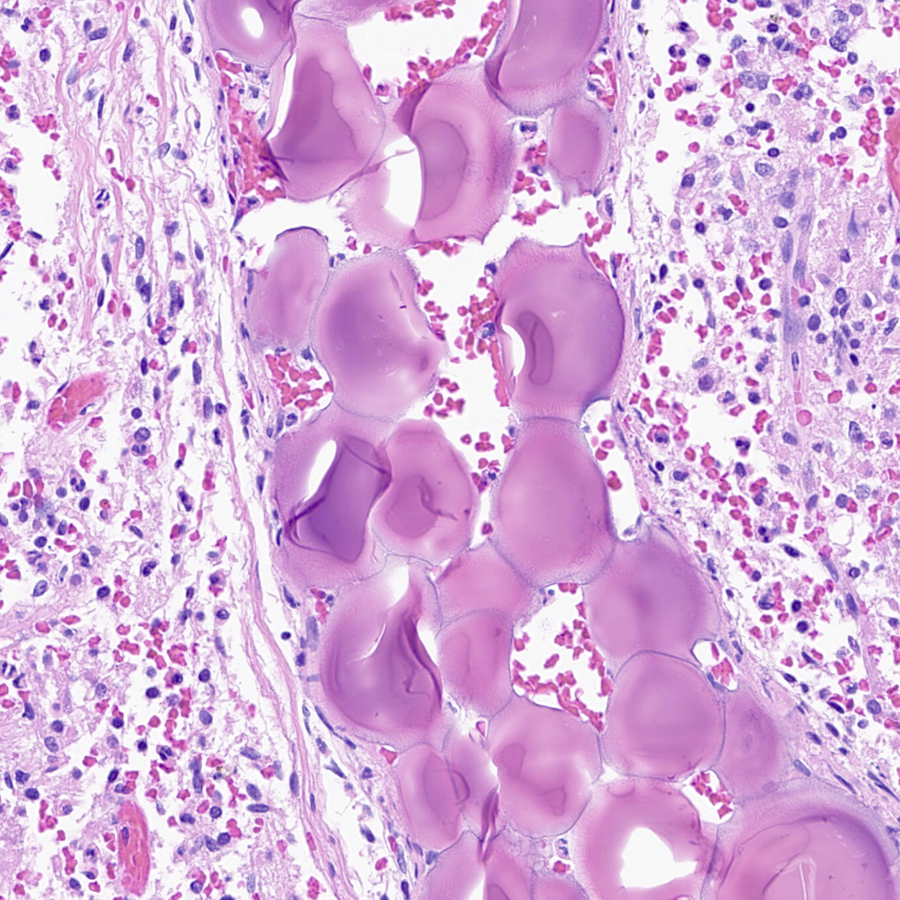

Dear #GIPath Routine gastric bx ,do you know what these eosinophilic structures are ? I think I saw once here in twitter that can be amyloid like that and a special name to this ?? I think this is called globular amyloidosis ,but have to prove it . Raul S. Gonzalez, MD

Yale Rosen Miruna Popescu, MD Celina Stayerman MD Jerad Gardner, MD 212/ Classic case. The empty spaces are a clue to the diagnosis. This diagnosis can 100% be made by pathology alone #pathology #pulmpath #pathx #pathbugs #crittersontwitter #PathTweetAward #idtwitter #tweetcyclopedia